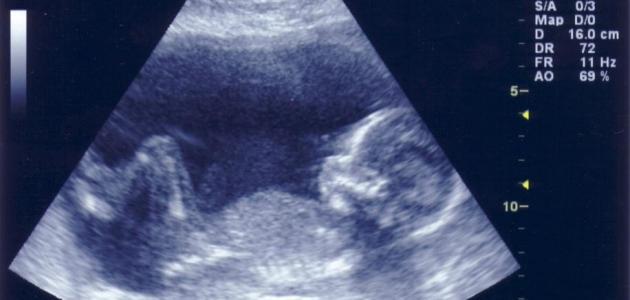

– طريقة جهاز السونار :

إن جهاز السونار يُعتبرطريقة مضمونة 100 لمعرفة نوع الجنين، فهذه هي أفضل طريقة حديثة على الإطلاق حيث يقوم الطبيب من خلاله رؤية الجنين ومن خلال التعرف على أعضاءه التناسلية يتم تحديد نوعه، وغالبًا يتضح ذلك أواخر الشهر الرابع أو الشهر الخامس من الحمل.